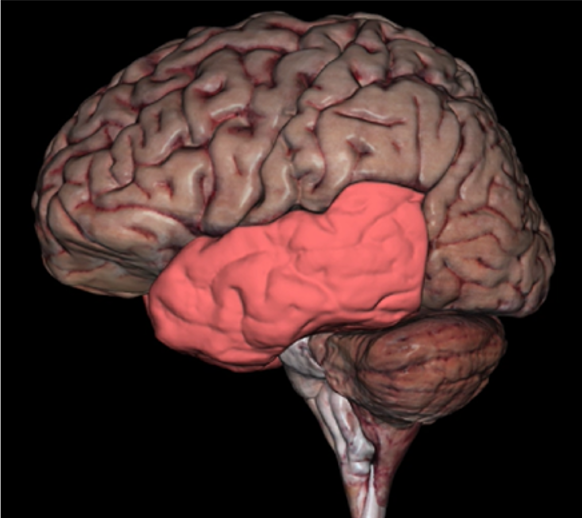

Temporal Lobe